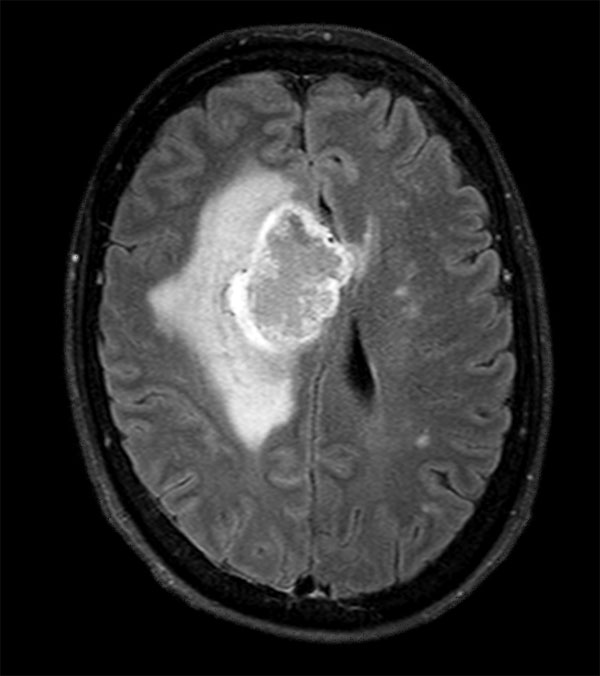

Advanced Neuro imaging - pCASL

Clinique Saint Joseph Imagerie Medicale, Liege, Belgium